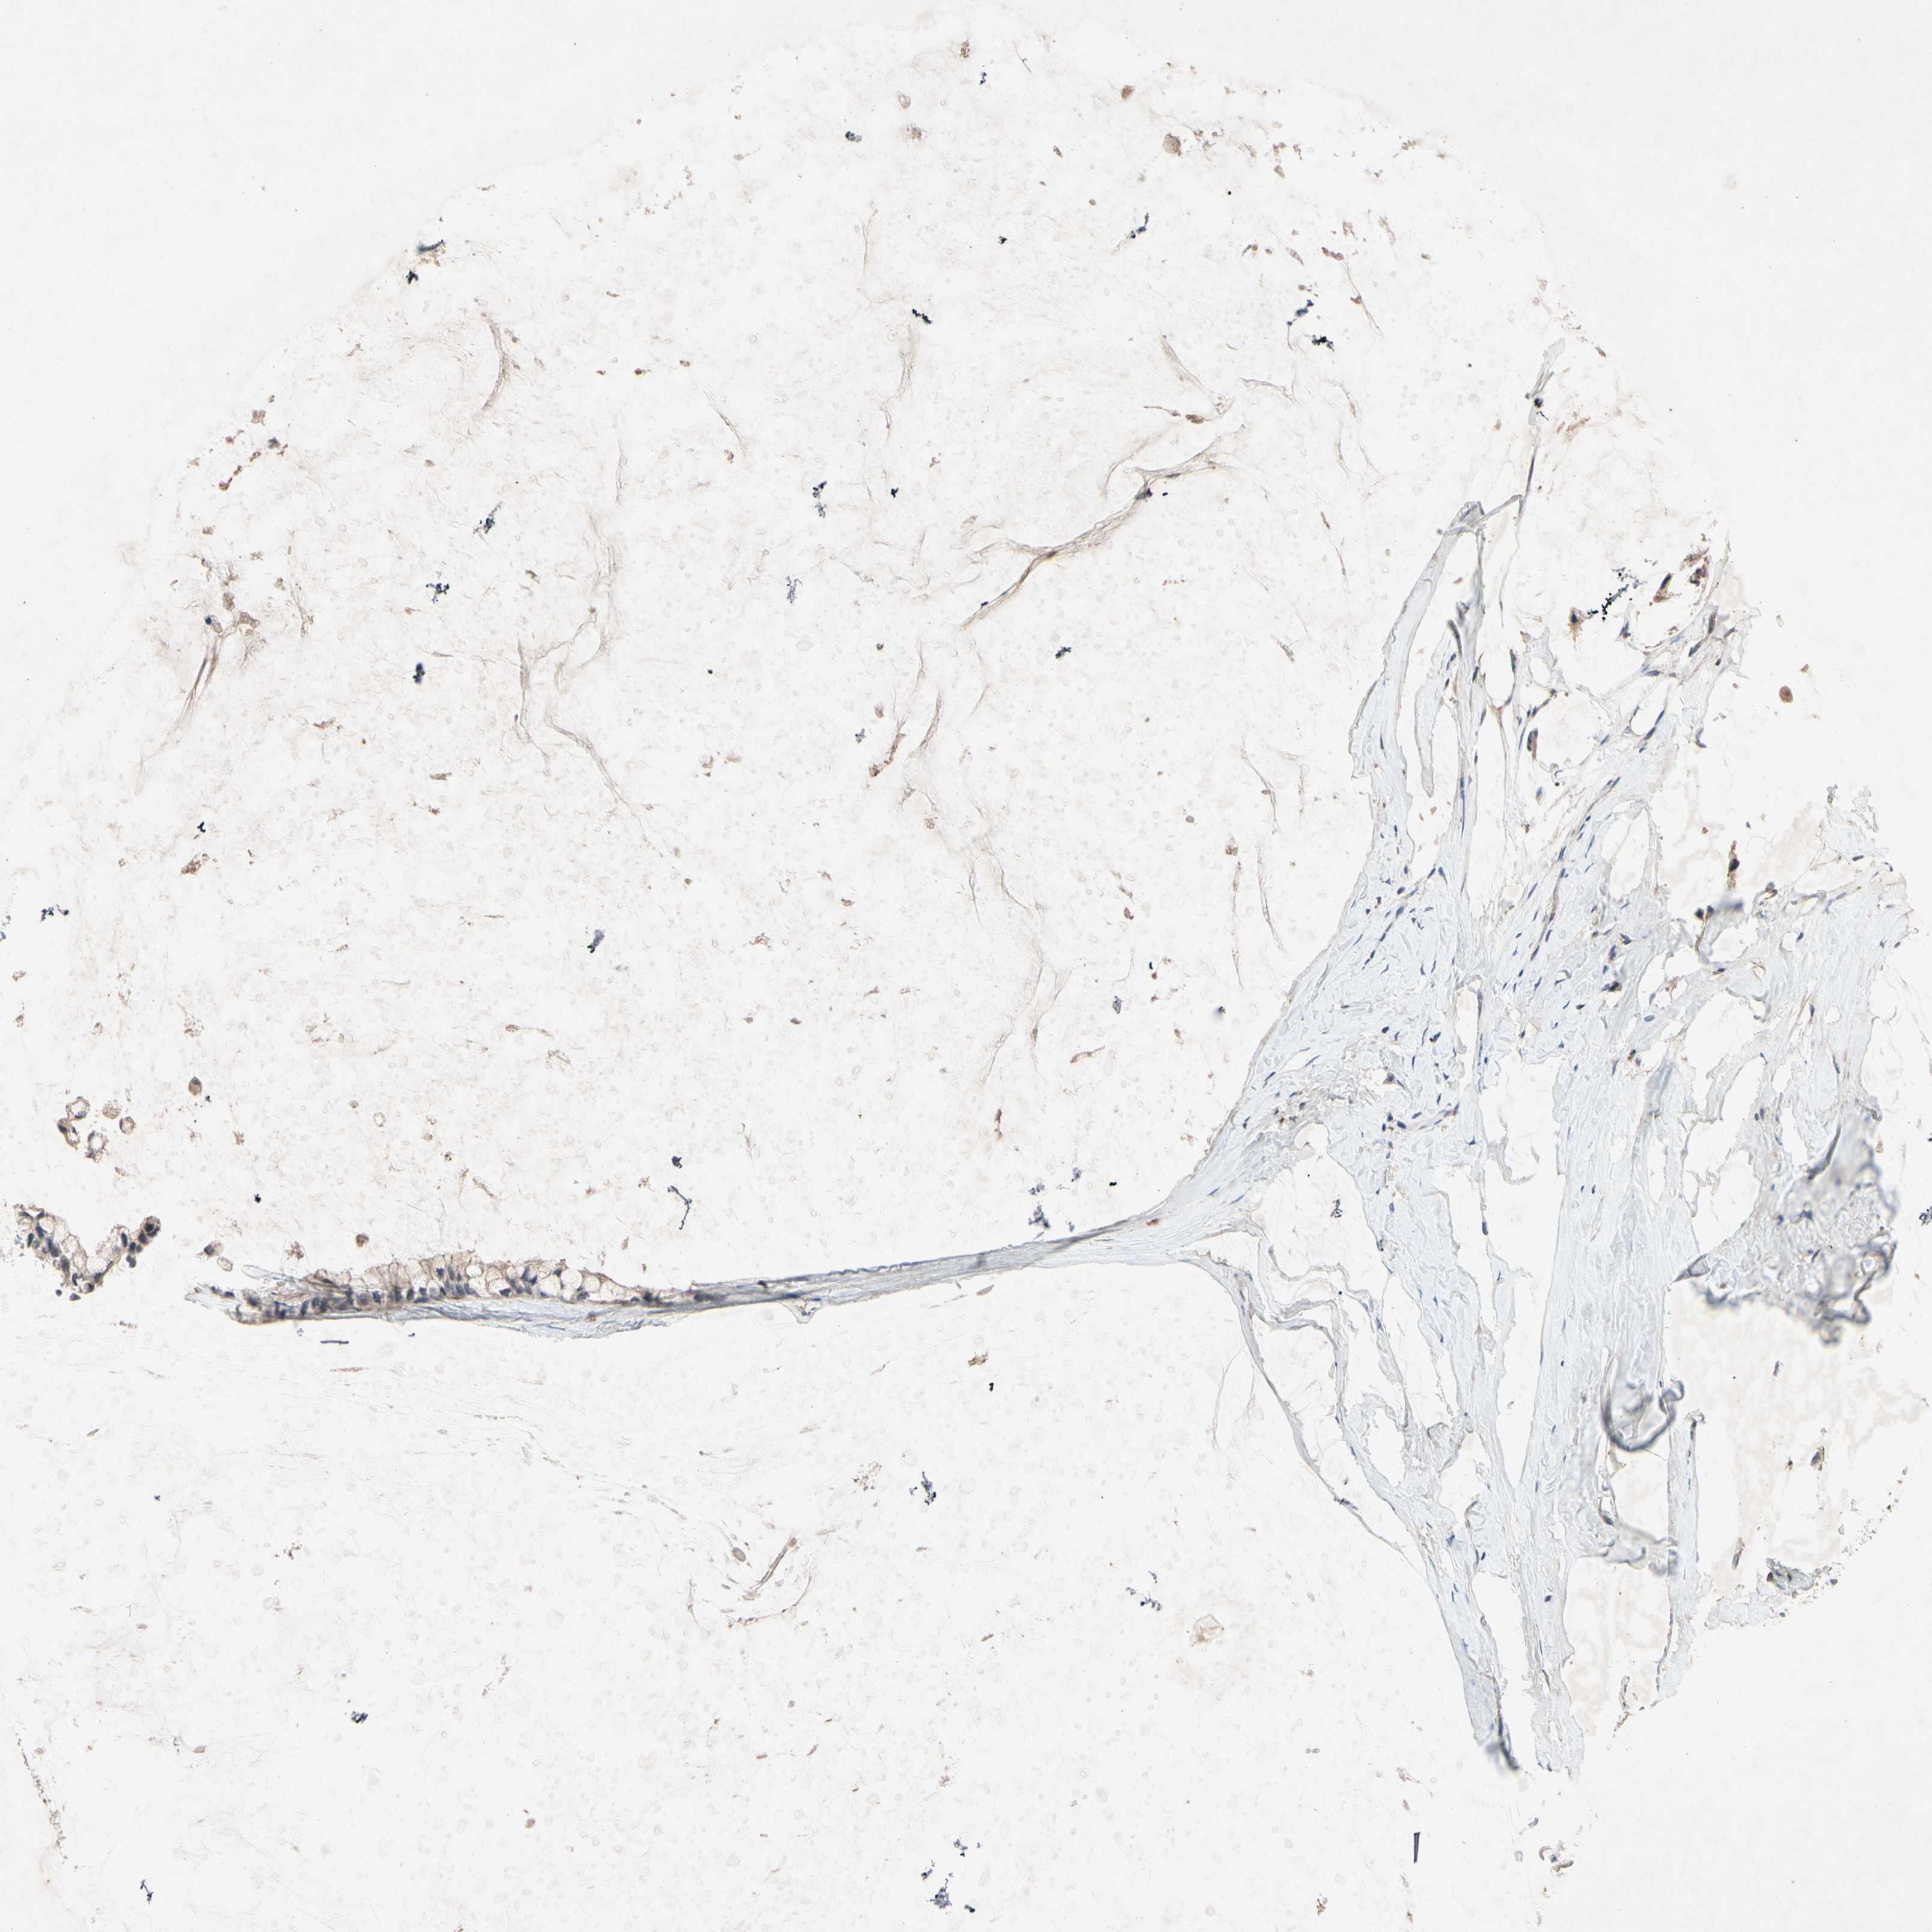

OVARIAN CANCER - Protein expressioni

A mouse-over function shows sample information and annotation data. Click on an image to view it in a full screen mode. Samples can be filtered based on level of antibody staining by selecting one or several of the following categories: high, medium, low and not detected. The assay and annotation is described here.

Note that samples used for immunohistochemistry by the Human Protein Atlas do not correspond to samples in the TCGA dataset.

Antibody stainingi

Antibody staining in the annotated cell types in the current human tissue is reported as not detected, low, medium, or high, based on conventional immunohistochemistry profiling in selected tissues. This score is based on the combination of the staining intensity and fraction of stained cells.

Each image is clickable and will lead to virtual microscopy that enables deeper exploration of all samples and also displays staining intensity scores, fraction scores and subcellular localization as well as patient and tissue information for each sample.

Antibody HPA007406

Antibody HPA007917

Cystadenocarcinoma, serous, NOS

Carcinoma, endometroid

Cystadenocarcinoma, mucinous, NOS

Carcinoma, NOS